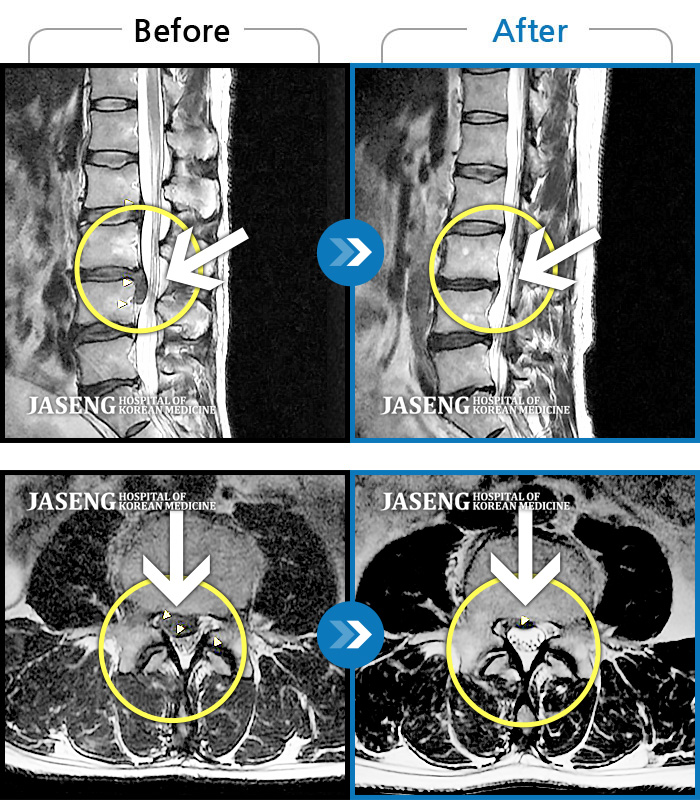

허리디스크

해운대 · 이상건 원장

허리통증, 좌측 다리 저림 및 근력 저하

촬영시기

2017.09.08 ~ 2018.05.11